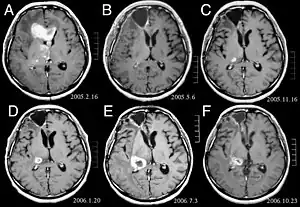

![]() (A) La imagen de RM muestra un tumor en los lóbulos frontales derecho y izquierdo, así como en el tálamo derecho. (B) RM después del tratamiento con resección quirúrgica, radioterapia y quimioterapia. El tumor ha desaparecido por completo, excepto por un ligero realce adyacente al margen quirúrgico. (C) Recurrencia del tumor talámico 9 meses después, a pesar de la quimioterapia de mantenimiento. (D) Crecimiento del tumor talámico dos meses después de la radioterapia estereotáxica. (E) Después de 6 ciclos de quimioterapia con temozolomida, la lesión talámica ha aumentado y el paciente presenta disartria y hemiparesia. (F) Después de 2 ciclos de tratamiento con interferón-beta y temozolomida, el tumor muestra una regresión parcial. | ||

En las imágenes de RM se muestra como una lesión sólida expansiva, mal delimitada, con edema perilesional asociado y que capta contraste. Histológicamente se caracteriza por atipias nucleares, aumento de la celularidad y significativa actividad proliferativa. La neoplasia se infiltra de forma difusa en el tejido circundante, sin destruirlo por completo, de manera que las estructuras afectadas aparecen engrosadas.[3]

La imagen de RM generalmente muestra una lesión sólida expansiva con edema asociado y captante de contraste. Puede ser difícil de distinguir del glioblastoma multiforme (GBM), por lo que es necesaria la confirmación histológica para un adecuado diagnóstico.